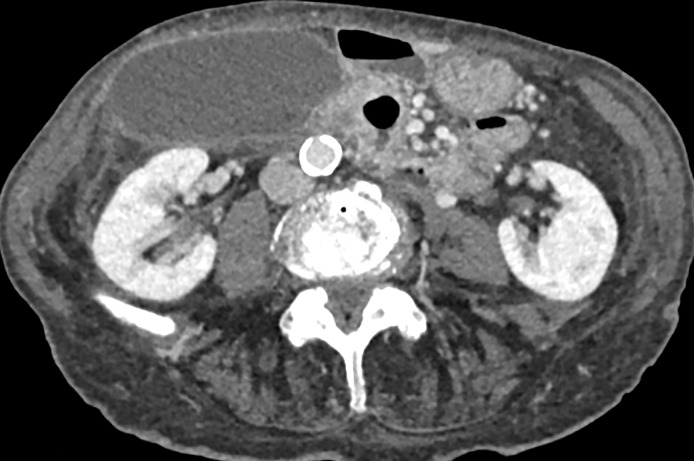

Teaching point: Gallbladder volvulus is a rare but serious diagnosis that needs urgent surgical treatment to avoid morbidity and mortality related to gallbladder ischemia and should be suspected in elderly female patients with acute right upper quadrant pain with imaging features including enlarged, abnormally positioned gallbladder and specific key findings on CT including "whirl sign" representing twisting of the cystic pedicle and "beak sign" at the gallbladder neck.

Abstract Image